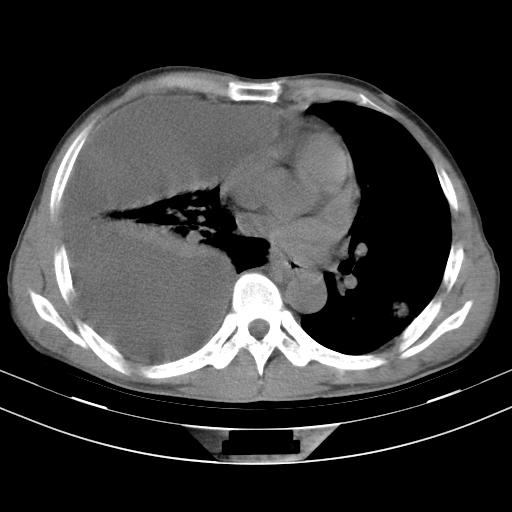

男性,44岁,结核病史多年。现胸闷气短,咳嗽,偶咳血。

右侧胸腔积液

右肺下叶不张

双肺多发结节影最分空洞形成考虑占位不除外结核

双肺陈旧性病变

1、右侧大量胸腔积液伴右肺压缩性膨胀不全,建议抽液治疗后复查 2、两肺继发性tb伴空洞形成。

1)两肺继发性肺结核伴空洞形成,左肺多发性结核球。2)右侧大量胸腔积液伴右肺部分膨胀不全。3)纵隔淋巴结肿大。